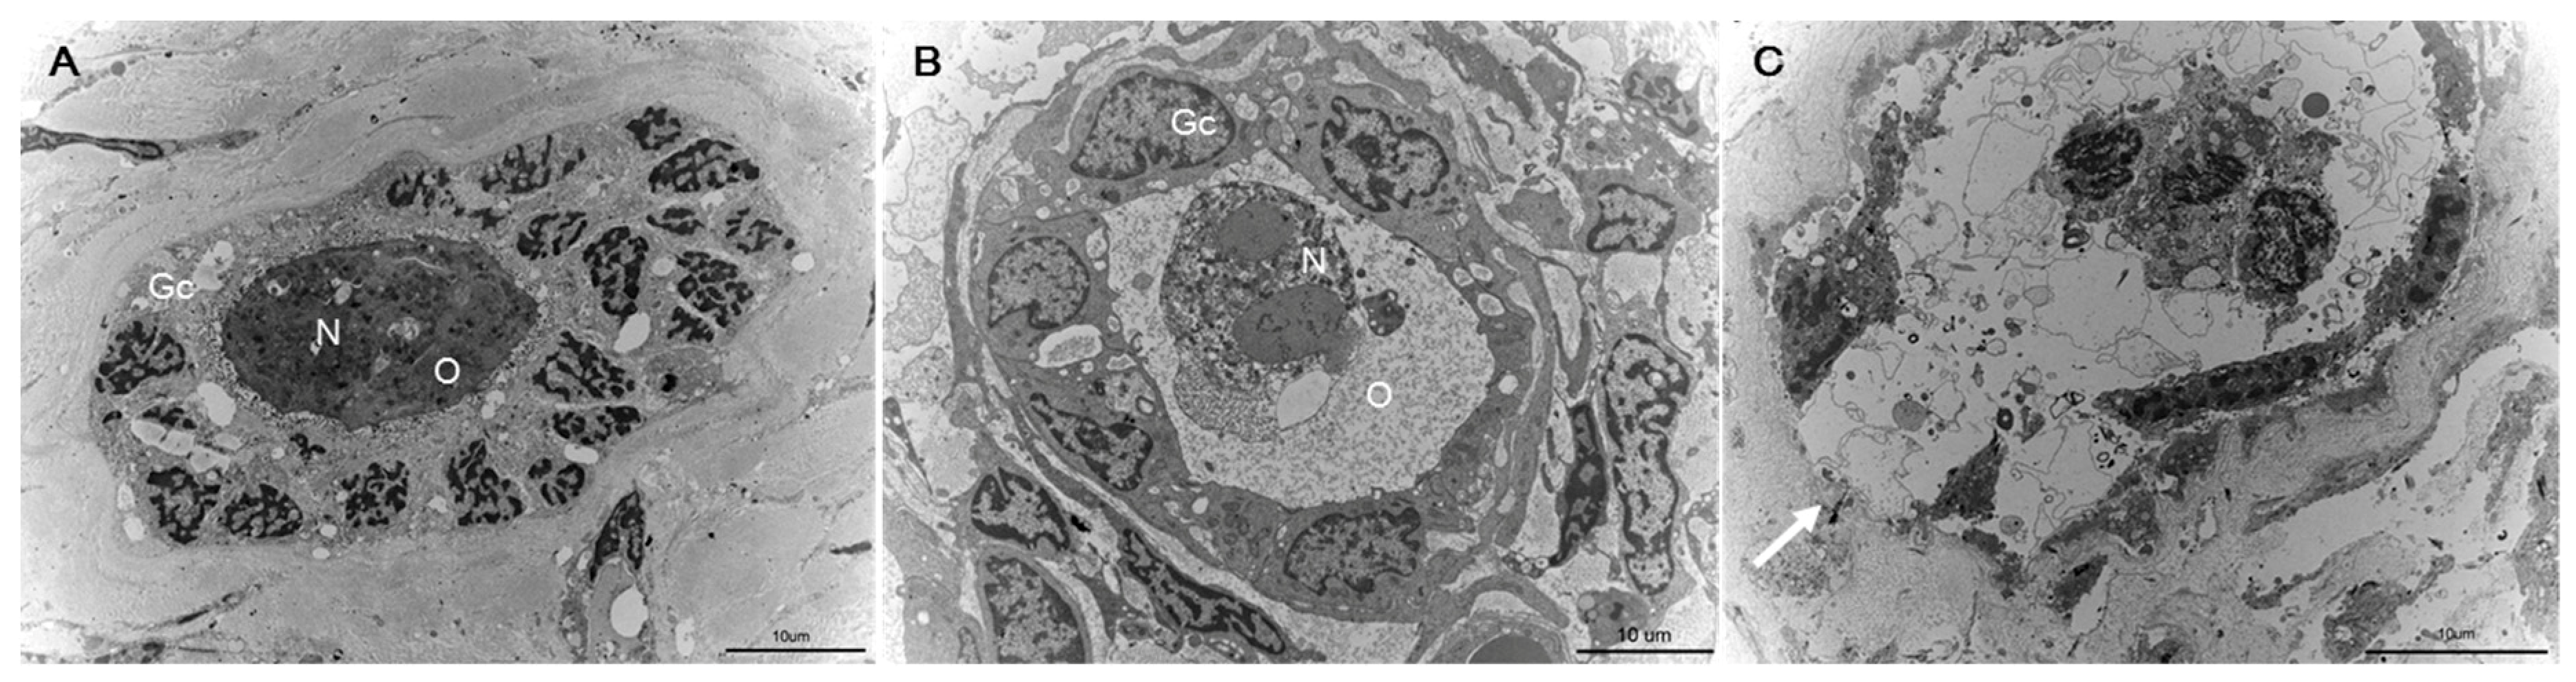

2.6. Fine Structural Evaluation by Transmission Electron Microscopy (TEM)